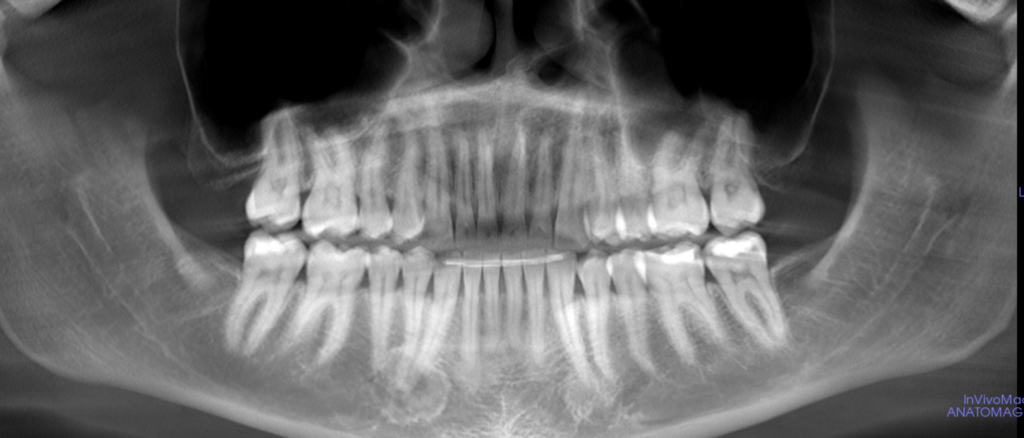

13-year-old girl with slow bilateral growth of the face

A 13-year-old girl was referred to the oral surgeon by a pediatric dentist due to slow bilateral growth of the face.